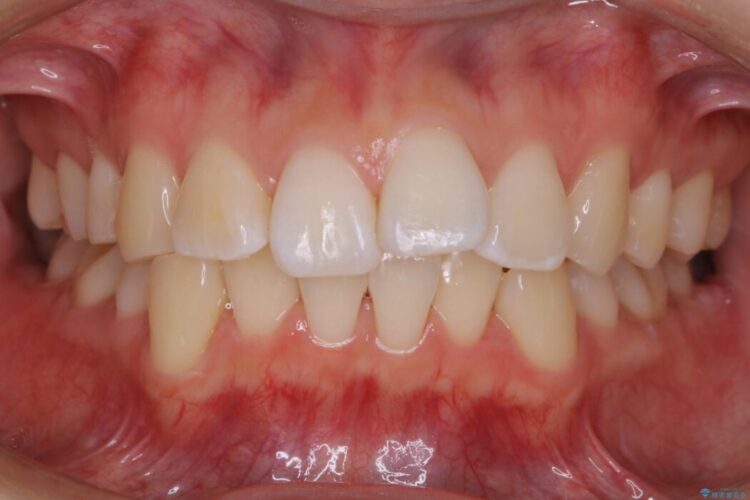

以前治療した抜歯矯正から後戻りをしてしまった歯列のがたつきを再矯正したいとのことで来院されました。

元々中学生から高校生にかけてワイヤー装置を用いた矯正治療をされた患者様でした。

大人になるにつれてライフスタイルの変化が生じ、歯が元の位置に戻らないように保定するためのリテーナーを継続使用することが難しくなったことから、歯列にがたつきが目立つようになったのでもう一度矯正治療をしたいとのご希望でした。

既に上下左右の4番目の歯が抜歯されているため、今回のケースでは非抜歯による歯の移動のみで矯正をしなければならず、難易度が高いものになりました。